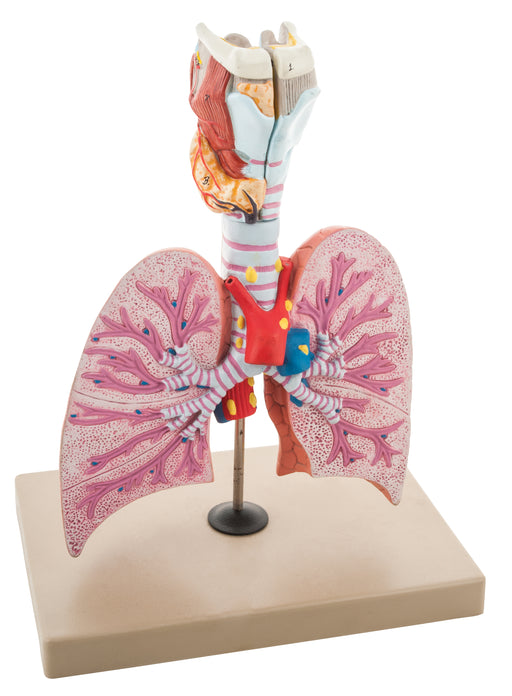

Respiratory - Healthy Lungs

With amazing attention to detail, this standing model maps the anatomy of a healthy lung. Designed to aid oncologists in helping their patients vis...

View full detailsAM16028